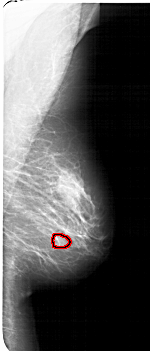

A_1770_1.RIGHT_MLO

FILE: A_1770_1.RIGHT_CC.OVERLAY

TOTAL_ABNORMALITIES 1

ABNORMALITY 1

LESION_TYPE MASS SHAPE OVAL MARGINS OBSCURED

ASSESSMENT 3

SUBTLETY 3

PATHOLOGY BENIGN

TOTAL_OUTLINES 1

BOUNDARY